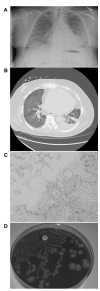

Strongyloides stercoralis is an intestinal nematode that can persist in the human host for decades after the initial infection and can progress to fulminant hyperinfection syndrome in immunocompromised hosts. We describe a patient who died of Strongyloides hyperinfection syndrome 2 months after orthotopic heart transplantation and discuss approaches to prevention, diagnosis, and treatment. Current practice guidelines recommend screening for and treatment of Strongyloides infection before transplantation, but physicians in the United States often miss opportunities to identify patients with chronic strongyloidiasis. Screening tests have limitations, and clinical suspicion remains an important component of the evaluation before transplantation. After immunocompromised patients develop hyperinfection syndrome, diagnosis is often delayed and mortality is high, so emphasis must be placed on screening and treatment before transplantation. We review current strategies for prevention, diagnosis, and treatment of chronic intestinal strongyloidiasis in patients who will undergo transplantation and discuss the clinical features and management of Strongyloides hyperinfection syndrome in transplant recipients.